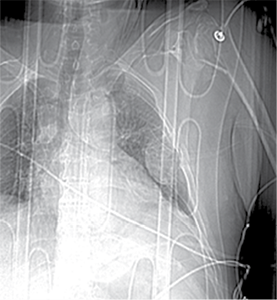

A 58-year-old patient was admitted to the Emergency Department of level I Trauma Center in August 2022 due to polytrauma sustained in a car accident. On arrival, the patient’s condition was severe, with decreased consciousness (GCS score of 12), unstable hemodynamic, subcompensated peripheral circulation, blood pressure of 62/32, and heart rate of 78 beats per minute. There was reduced breathing on the left side with a respiratory rate of 18 breaths per minute and an oxygen saturation (SpO2) of 85.0%. Palpation revealed pain in the left posterior chest. X-rays and CT scans were performed, which revealed a traumatic hemothorax on the left side, humeral head within the pleural cavity, three rib fractures, lung contusion, and hematoma.

Neurovascular status of the left hand was intact. The patient’s condition was stabilized in the intensive care unit and after 5 days transferred to the Thoracic Surgery Department, where 4 days later a resection of the fifth rib, thoracoscopic removal of the humeral head, and lung decortication were performed.

Figure 1. First X-ray and computer tomography upon admission (with humeral head shown)